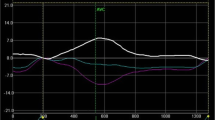

A significant increase in peak base-apex torsion was found in HCM mutation carriers with respect to controls (p = 0.001) (Table 3, Figure 2), while peak circumferential strain was similar. Hence, TECS-ratio was significantly increased in the carrier group (Figure 2).

No significant differences could be detected in peak systolic and diastolic torsion rate, after correction for peak torsion. This is also shown in Figure 3, which visually outlines that increased torsion is accompanied with a similar increment of (uncorrected) torsion rates. There was no significant difference between torsion measured at different levels (base-mid, mid-apex) of the LV (data not shown).

Remarkably, non-hypertrophied HCM carriers show similar contraction patterns including a relative increase in LV torsion with respect to subendocardial circumferential contraction (e.g. increased TECS-ratio). It was expected that, due to the elevated ejection fraction in carriers, torsion and subendocardial circumferential strain (which is related to ejection volume) values would show parallel increments, resulting in unaltered TECS-ratio. Apparently, impairment of subendocardial contraction of myofibers changed the balance between torsion and ejection in mutation carriers irrespective of LV wall thickness.

Except for myocardial disarray and/or disturbed regional myocardial perfusion as potential explanations for the relatively impaired subendocardial fiber shortening, other factors might be affecting LV torsion in HCM mutation carriers. Interestingly, mutation carriers showed a (slightly) increased ejection fraction (causing the difference in TECS to be less pronounced than the difference in torsion alone (Figure 2)), which is also a common finding in manifest HCM [38].